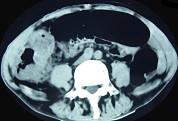

问题 男,70岁,右下腹胀,腹痛,腹泻,影像检查如图,最可能的诊断是 ( )

选项 A.结肠克隆恩病 B.结肠癌 C.结肠套叠 D.结肠结核 E.结肠淋巴瘤

答案 B